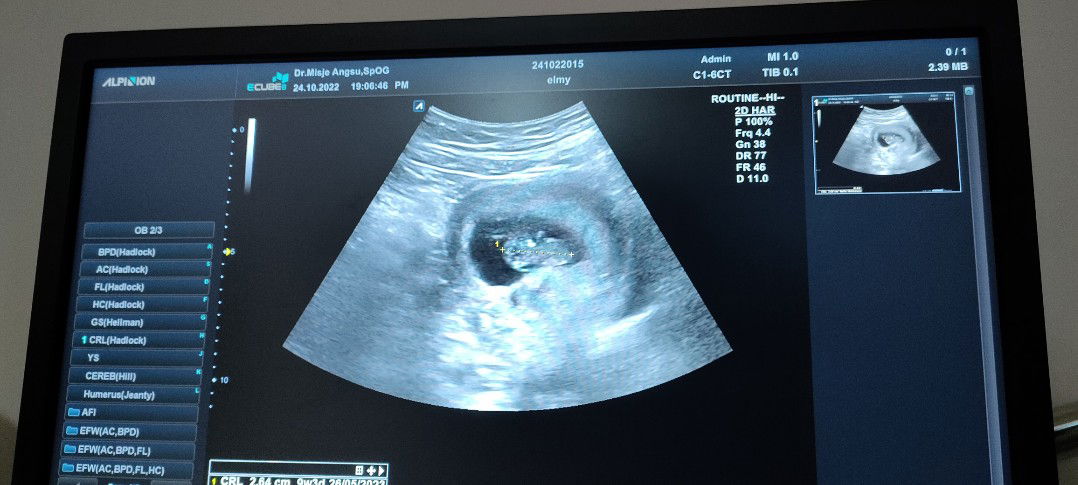

aku kmren 35 Minggu bbj 2,1 Bun di hasil USG nya tp dokternya bilang 2,5 jd yang bener tuh yang mana ya Bun?

rus gmn bun .. barusan aku usg juga 35w 0day bb 2.2 disuruh usg fetomaternal krn takut ada masalah di janinnya. krn bbkurang dan ketuban sedikit 🥺

Pas Usg 34w kemarin Bbj 2.200kg bun. sekarang masuk 36w belom Usg lagii